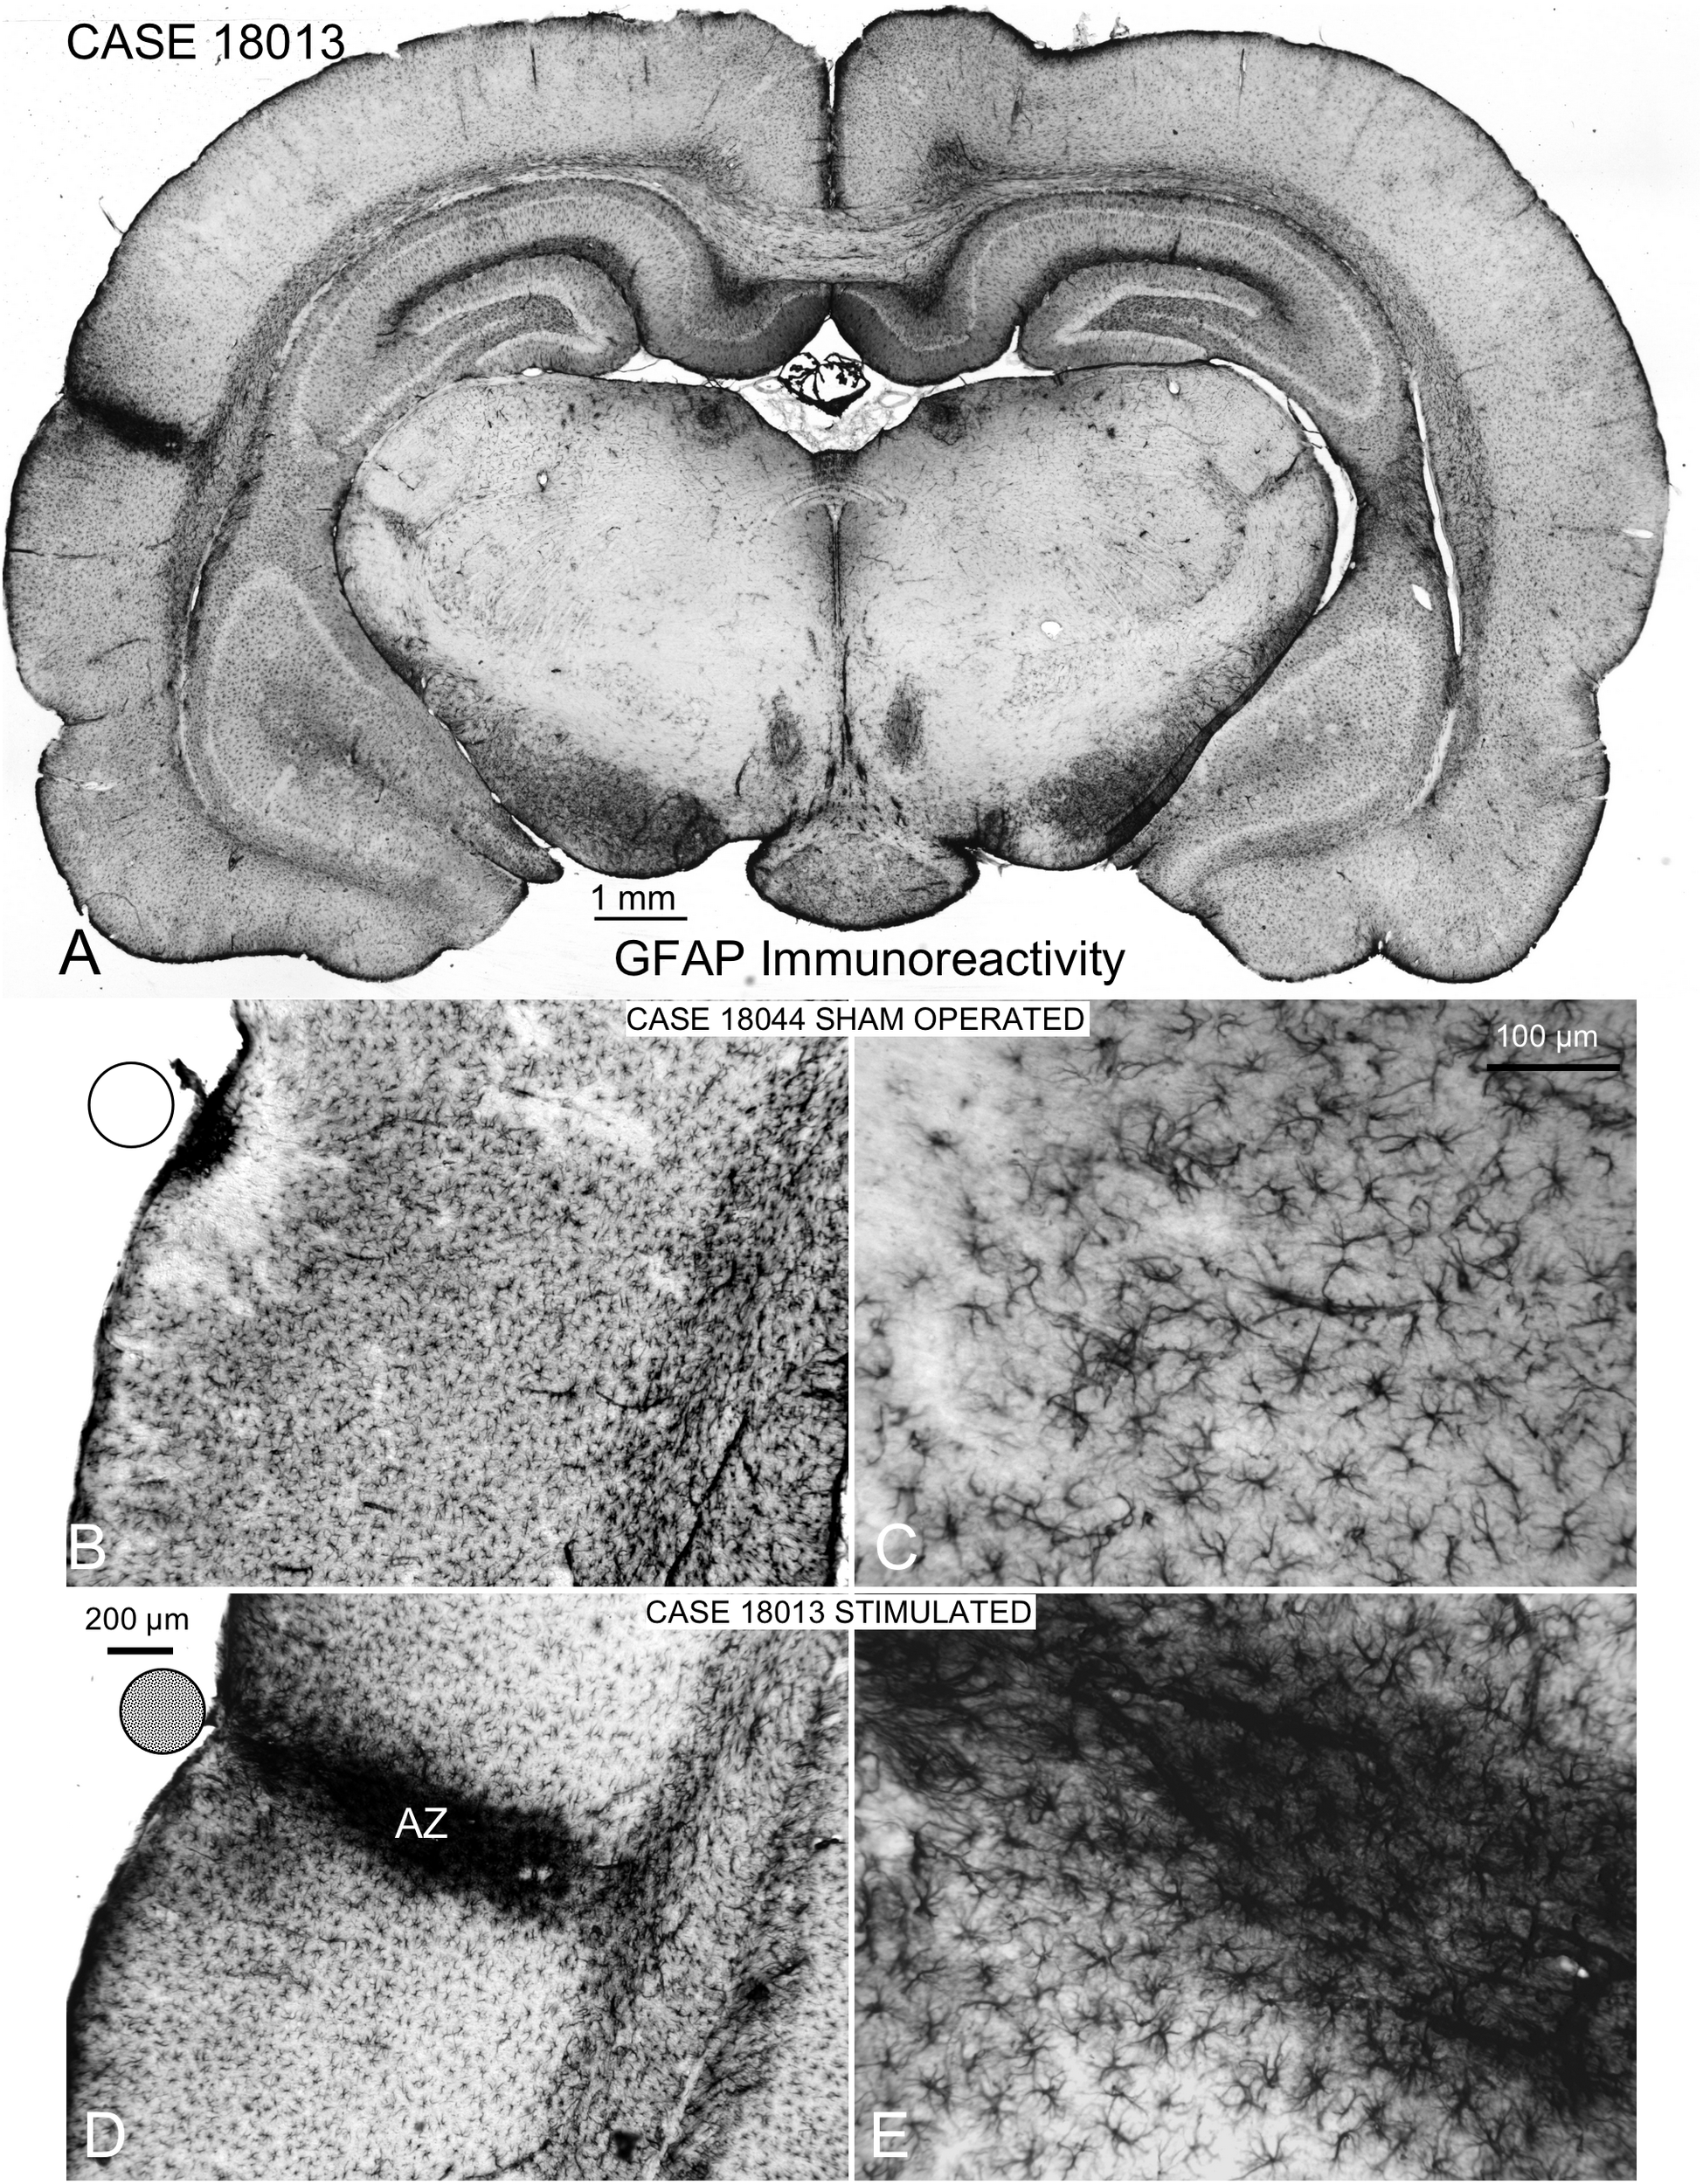

Localization and Assessment of EES Effects: GFAP Immunoreactivity

Coronal sections showed a small deformation of the surface, both in sham-operated (group 2) and in multisession EES (group 4) animals, in the region of contact of the electrode with the dura (Figures 7A,B,D). The analysis of the thickness of the cortex from sham-operated rats (Figures 8A,B) showed a decrease in immunoreactivity restricted to a superficial, thin band affecting layers 1–3, with no detectable astroglial architectural reaction along cortical layers (Figures 7B,C). However, in sections of multisession-stimulated animals, a highly dense immunoreactive area of positive astrocytes and blood vessels was identified throughout the thickness of the cortex (Figures 7A,D,E). GFAP-positive glial cells and blood vessels allowed us to easily delimitate a potential area of predominance of electric field effects (AZ; Figure 7D). Astroglial cell expansions appeared orthogonally oriented, either to the surface of the brain or to perforant arteries (not shown). Extensive, dense interstitial immunoreactivity was also identified in ribbons around brain ventricles, white matter (Figures 8C,D) and around larger blood vessels (Figure 8C inset). After superimposition of coordinates taken from GFAP immunostained serial sections over a macroscopic lateral surface view of the rat brain, AZ reactive astroglial areas were always shown positioned inside the AC cytoarchitectural borders (Figure 9). Average of measurements of the surface area of the AZ (group 4) was 4.21 ± 2.06 mm2 (Figure 9).

Figure 7. GFAP immunocytochemistry of coronal sections of multisession-stimulated and sham-operated rat brains. (A) Panoramic view of a case of the multisession protocol group, which shows a restricted cortical intramural increase in immunoreactivity where the stimulation electrode is located (on the AC). (B,C) Sham-operated control showing a small, dense immunoreactive area in the surface and a restricted, superficial band devoid of labeling. (D,E) Active zone (AZ) of electric stimulation. Note the intense staining of astrocytes and blood vessels inside AZ.